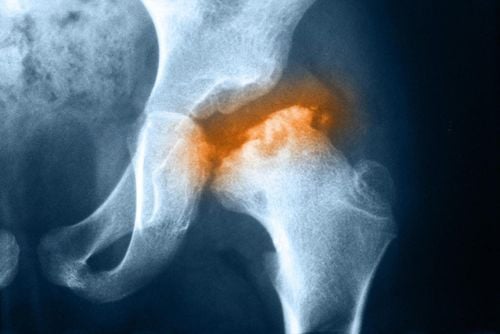

Hoại tử chỏm xương đùi có thể tàn phế nếu không được chữa trị triệt để

Hoại tử chỏm xương đùi làm cho chỏm xương đùi bị hoại tử do thiếu máu nuôi. Quá trình này tiến triển tăng dần và ảnh hưởng đến xương dưới sụn đến bẹp chỏm xương đùi có thể dẫn tới tàn phế nếu không được điều trị triệt để.

Hoại tử chỏm xương đùi do thiếu máu nuôi

Hoại tử chỏm xương đùi do thiếu máu nuôi có thể dẫn đến mất chức năng của khớp háng, thậm chí gây biến chứng tàn phế. Vì vậy, phát hiện và điều trị sớm đóng vai trò rất quan trọng trong việc giảm thiểu nguy cơ biến chứng của bệnh.

Bệnh hoại tử xương là gì?

Bệnh hoại tử xương là tình trạng xương bị nhồi máu khu trú, có thể tự phát hoặc do nguyên nhân cụ thể. Xương bị hoại tử sẽ gây đau, giới hạn vận động, gây phá hủy khớp và biến dạng khớp. Các tổn thương xương bị hoại tử nhỏ có thể tự lành, nhưng các tổn thương lớn, nhất là khớp háng sẽ tiến triển nặng hơn nếu không điều trị.